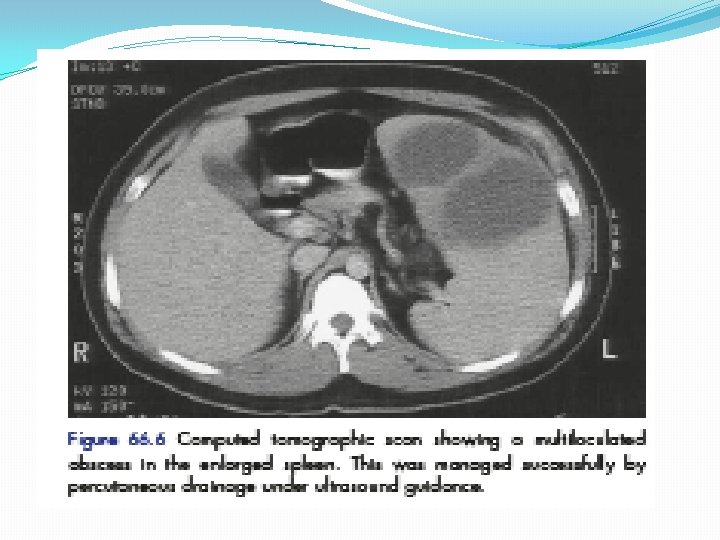

Splenomegaly and hypersplenism Infective BACTRIAL : Typhoid , PT Biogenic abscess VIRUS Spirochete s Parasite Bilharzia, Malaria Salazar Blood disease NEOPLA CONGES COLLAG TIVE STIC METABO EN POTAL LYMPHOMAP FELTY DISEAASE HYPERTENSION LIC Leukemia HEMANGIOMA Anemia Polycythemia SARCOMA ITP Hemolytic anemia GOUCHER DISEASA AMYLODOSIE RICKETS 9 TILL’S disease